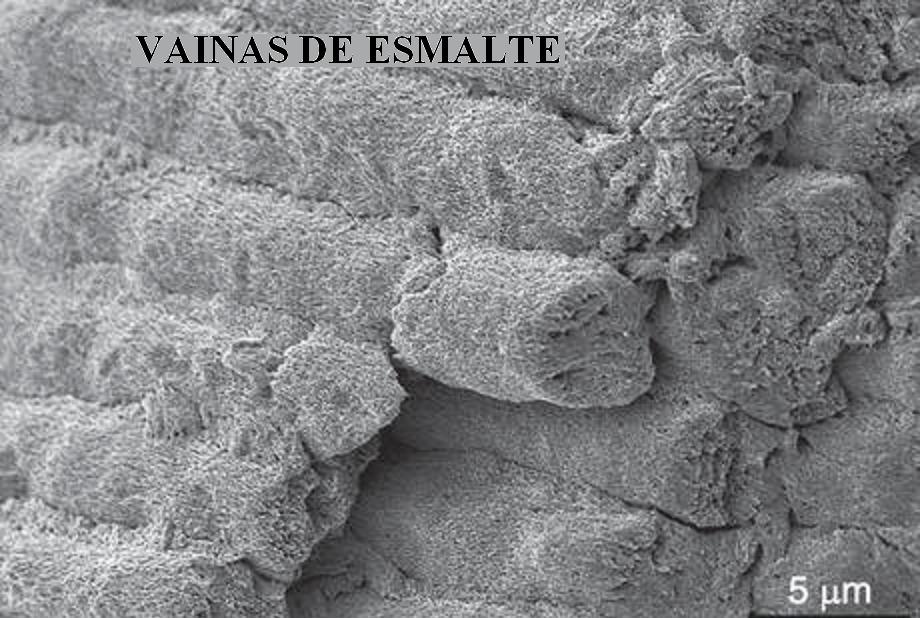

El mineral primario del esmalte es la

hidroxiapatita, que es un fosfato de calcio

cristalino.(cristales de hidroxiapatita CHAP que

confluyen en PRISMAS de esmalte; a su vez estos

primas se agrupa para formar VAINAS de esmalte.)

Ver imagen inferior.

VAINAS DE ESMALTE